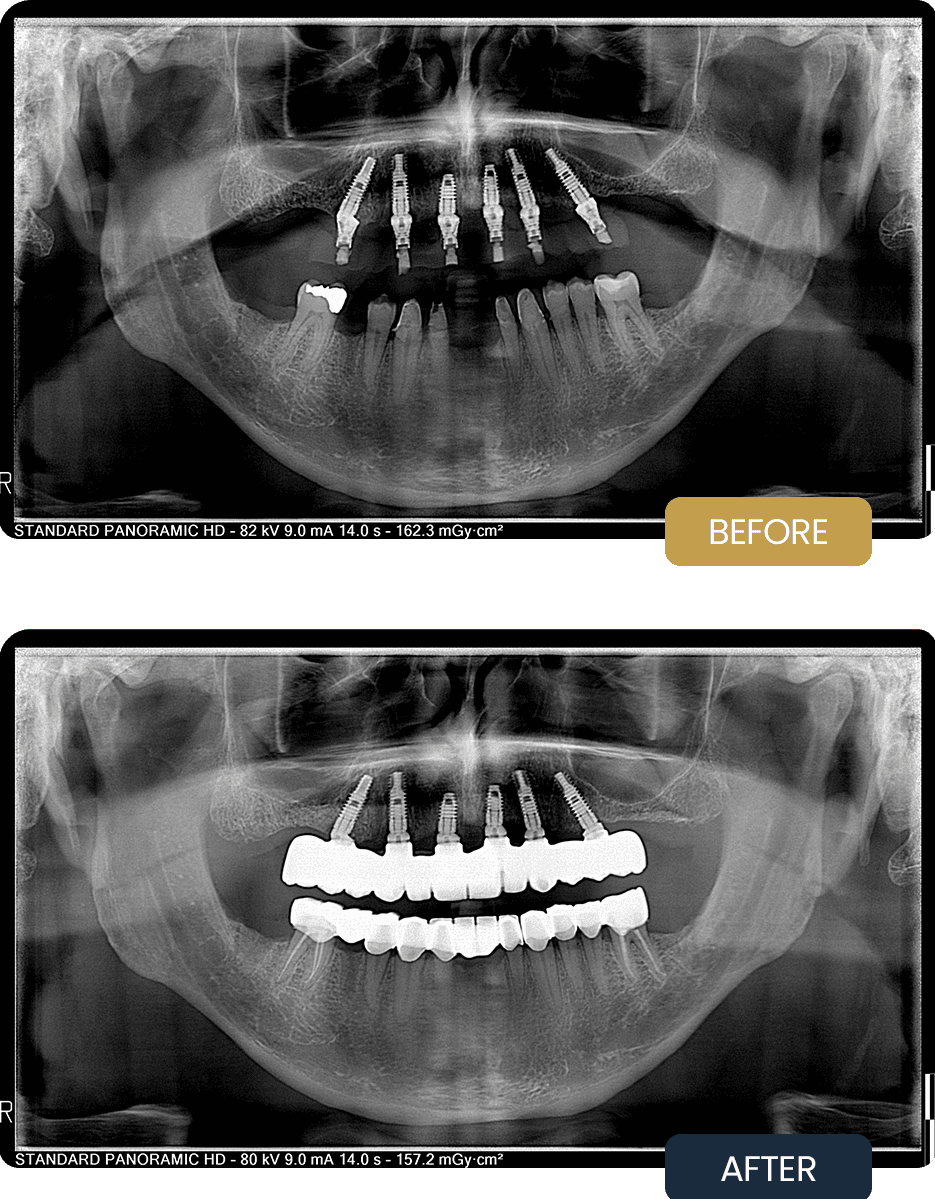

At initial presentation, Stuart exhibited significant tooth loss and reduced functional stability in the upper jaw, alongside compromised and heavily restored teeth in the lower jaw. Chewing efficiency and comfort were notably affected.

The pre treatment panoramic radiograph illustrates the extent of dental deterioration and the need for a comprehensive implant supported solution in the upper jaw, combined with targeted restorative care in the lower jaw.

Post treatment panoramic imaging confirmed successful integration of all six implants in the upper jaw with stable positioning of the full arch prosthesis. In the lower jaw, restored teeth showed improved structural integrity and balanced occlusion following extractions, root canal treatments, and crown placement.

Following treatment, Stuart regained effective chewing function, improved comfort, and long term stability through a carefully planned combination of implant and restorative dentistry designed for durability and predictable performance.